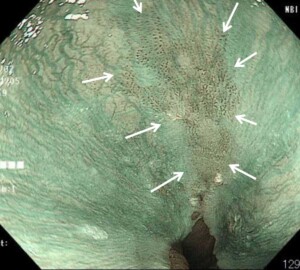

②早期胃がん

古い内視鏡機器では見逃していたかも知れません。

通常ではほとんどわからず、ごくわずかな光の反射の違いや色調の違いでがんを

発見しました。インジゴカルミンという青い色素をかけるとはっきりしました。

内視鏡治療で完治できました。

*インジゴカルミン撒布